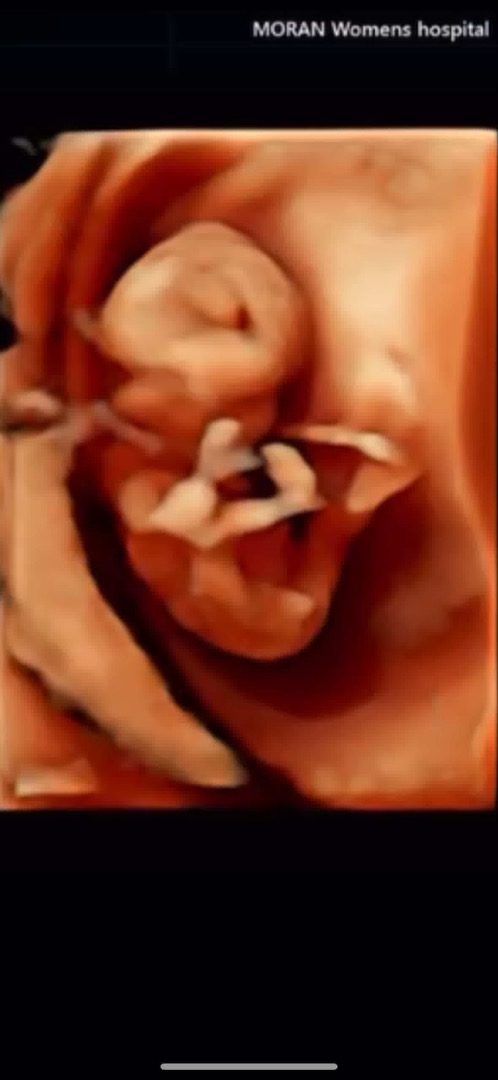

안녕하세요! 지금은 13주인데 저때 1차 기형아 검사 받느라고 정밀 초음파를 했는데 저기 다리 사이에 튀어나온거 고추 맞나요? 저는 아들이기를 바라기도 해요ㅠㅠ 12주1일 치거 이쁜 자세를 너무 잘 보여준다고 정밀 해주시는 분이랑 원장님께서 그러시더라고요.. 너무 활기차다구.. 혹시 중간 저거 나중에 사라지나요ㅠㅠ?

12주1일